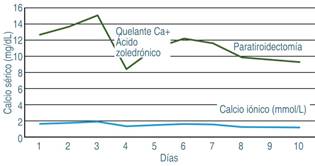

Un aspecto que llamó la atención fue la persistencia de elevación de calcio sérico (hasta 15.0 mg/dL) y calcio iónico (2.0 mmol/L), por lo que se iniciaron medidas antihipercalcemia con manejo de líquidos a 2,500 mL/m2/SC y diurético de asa durante 48 h. Ante la falta de respuesta, se decidió administrar ácido zoledrónico, como quelante de calcio. Por lo anterior, se solicitó determinación de paratohormona en sangre siendo el valor de 314.4 pg/dL (normal 10-55 pg/dL). Además, el fósforo sérico fue de 4.26 mg/dL, se detectó hipercalciuria y niveles séricos de vitamina D en 6.8 ng/dL (normal de 30-40 n/dL).

El paciente permaneció en la UCIP durante 10 días hasta la resolución del estado de gravedad. En cuanto se obtuvo mejoría, se decidió realizar paratiroidectomía de las glándulas paratiroides superior e inferior derecha. Tras el evento quirúrgico, se obtuvo normalización de los niveles de calcio y de los niveles de paratohormona. El reporte histopatológico fue de un adenoma paratiroideo. En la Figura 2 se muestra la evolución del calcio sérico y iónico durante 10 días.